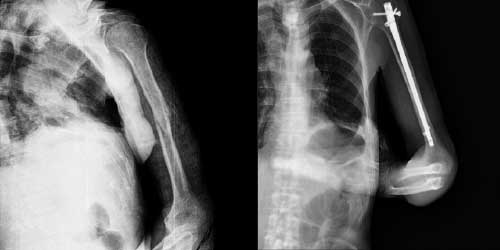

Omurga metastazı, kanserin ilk olarak iç organlarda gelişip daha sonra omurga kemiklerine yayılması sonucu oluşan bir durumdur. Çoğunlukla kan yoluyla sıçrayan bu tür metastaz, hastalarda sırt ve bel ağrısı gibi şikayetlerle kendini gösterir. Erken teşhis ve uygun tedavi yöntemleri, hastaların yaşam kalitesini artırmada kritik bir rol oynar.

Tedavide başarıyı artıran en önemli etkenlerden biri ameliyat öncesi iyi bir hazırlık ve cerrahi planlama yapmaktır. Her şeyden önce tanı doğru konmalı. Bunun için hasta iyi dinlenip, detaylı muayene edildikten sonra tetkikleri dikkatli incelenmelidir.

Her ameliyatın olduğu gibi kemik ve yumuşak doku tümör ameliyatlarının da riskleri vardır. Bu riskleri genel ve yapılan ameliyata özgü olmak üzere kabaca iki başlık halinde gruplandırabiliriz. Öncelikle anestezi ile ilgili risklerin anestezi uzmanı tarafından (...)

Ameliyat sonrası takip ve kontrol hastanın ameliyat masasında uyanması ile başlar. Özellikle damar ve veya siniri ilgilendiren ameliyatlarda hasta ameliyat masasından alınmadan ekstremitenin dolaşımı ve ilgili sinirin fonksiyonu kontrol edilir.